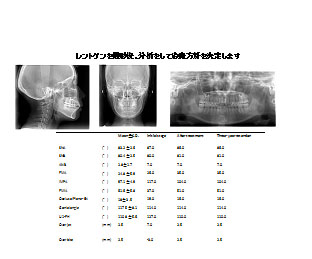

2018/08/29 矯正の低被爆レントゲン

池袋よりひとつ隣駅の東京都豊島区大塚駅すぐの大塚たまみ矯正歯科では、 矯正治療前に…